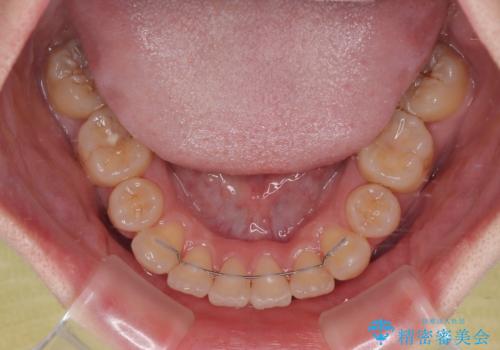

- 矯正装置

- 審美装置

口元の突出感はなかったものの、捻転や八重歯を改善するために補助装置を併用する必要がありました。

予定の2年半を越えてしまいましたが、無事にきれいな口元に仕上げることができました。